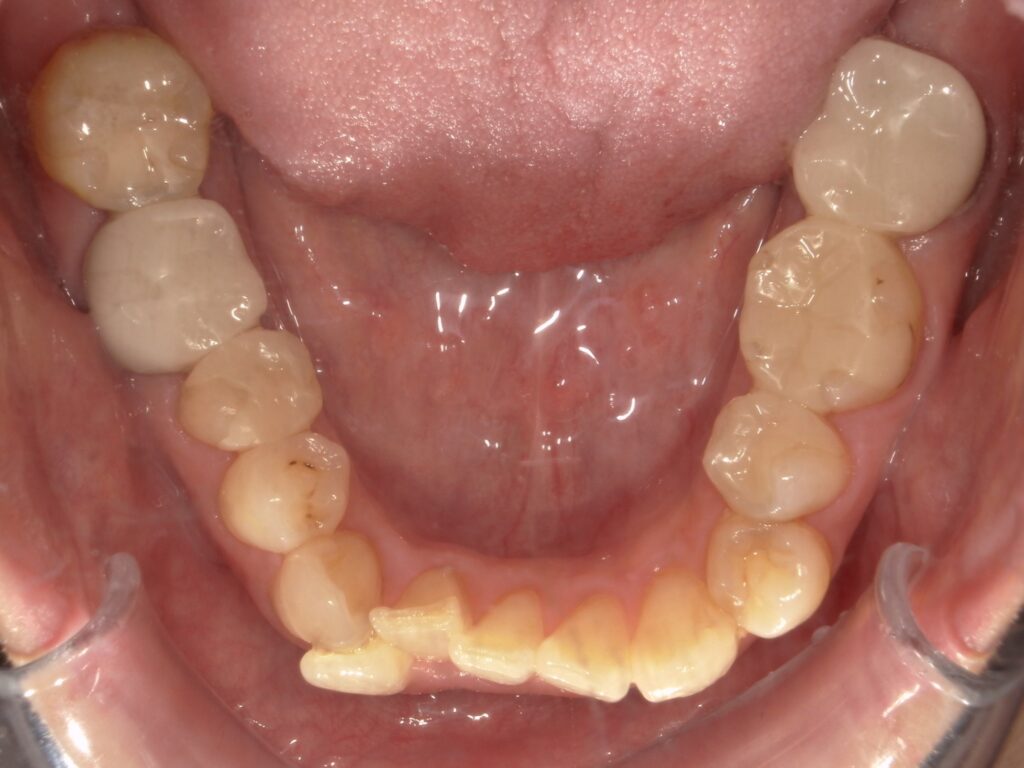

Before

After

ガタつき

- 40代女性

- 主訴:ガタつき

- 矯正方法:インビザラインの抜歯矯正

- 治療期間:11ヶ月

- 治療費:935,000円

- その他ご要望:差し歯があるが矯正できるか、かぶせ物が多いので矯正に影響ないか、金属アレルギーあり。

- 詳しくはこちら

ご相談内容 ガタつきが気になると40代女性からのご相談 現状と治療方針 ガタつきが見られます。特に下の前歯の右側の2番目の歯は完全に並ぶスペースがありません。そのため、下の歯を1本抜歯して治療を行いました。 治療結果 ガタつきを11ヶ月で改善することができました。 振り返り 今回の患者様はガタつきが強く、顎のスペースに対して歯が並ぶスペースが不足していたため、片側の抜歯矯正を行いました。上の前歯2本が差し歯のため、歯が動くのか心配されていましたが問題なく動いています。また、かぶせ物が多いことも矯正に影響がないか気にされていましたが、こちらも問題なく治療は順調に進みました。金属アレルギーでしたがマウスピースのため問題なく矯正することができました。 リスク・副作用 マウスピースの装着時間を守っていただけないと矯正治療に時間がかかり、場合によっては治療がうまく進まない可能性があります。